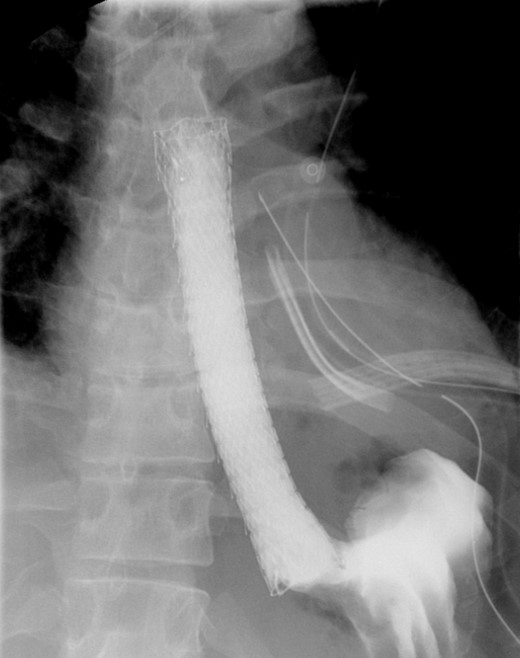

A computed tomographic scan revealed air and fluid surrounding the esophagus (Fig. 1). Esophagogram performed with water-soluble contrast media showed a distal esophageal perforation with a free leak into a large mediastinal cavity to the left of the esophagus (Fig. 2). The patient was triaged directly to the operation room. A left chest tube was placed with improvement in his oxygenation, and grossly murky fluid was drained. Esophagogastroduodenoscopy (EGD) was performed next and revealed a very small caliber esophagus with concentric ringed appearance. A tight stricture was noted in the mid-esophagus, which only allowed passage of a pediatric gastroscope. In the lower esophagus, a 2-cm tear with necrotic edges was visualized 3 cm above the gastroesophageal (GE) junction. With this diffusely strictured and very diseased appearance of the esophagus, the decision was made to proceed with stent placement and thoracoscopic drainage of the mediastinum rather than primary surgical repair via thoracotomy. A fully covered, 15 cm × 19 mm, EndoMAXX® esophageal stent was successfully placed covering the perforation site. Mediastinal washout and drainage was performed subsequently via left thoracoscopy. A postoperative esophagram showed no leak and the patient was started on a liquid diet that was tolerated well. His hospital stay was uneventful, and he was discharged on twice daily high-dose proton pump inhibitor (PPI) on post-operative Day 5. He was placed on a mechanical soft diet on discharge. Repeat upper GI study with water soluble contrast postoperatively showed no evidence extravasation. (Fig. 3)

Shows evidence of esophageal rupture and leak with pneumomediastinum and air and fluid surrounding the esophagus.